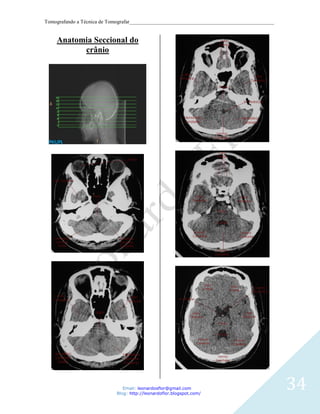

Anatomia Seccional do

crânio